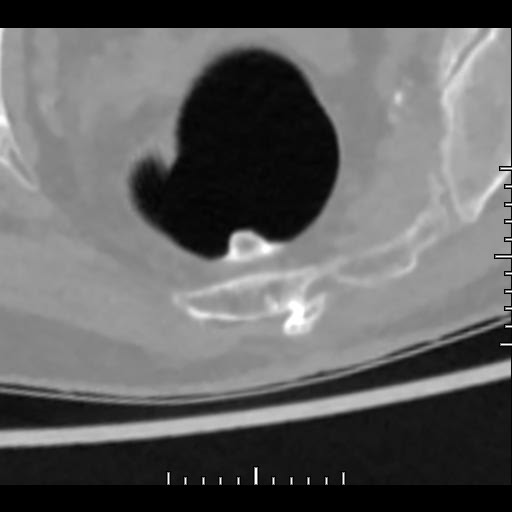

De nouvelles approches tendent à se généraliser, dont l’une est particulièrement intéressante : la coloscopie virtuelle. Elle consiste en une exploration scanographique permettant d’analyser l’intérieur de la cavité recto-colique.

Son avantage : elle ne nécessite plus l’insertion d’un endoscope, l’instrument utilisé dans la coloscopie optique, pour rechercher des lésions à risque de cancer colorectal, essentiellement des polypes.

Dans ces conditions, la coloscopie virtuelle est un formidable outil de dépistage, avec une fiabilité proche, voire dans certaines conditions, supérieure à la vidéocoloscopie ([2]).

A l’Institut de Radiologie de Paris, l’examen consiste en un scanner abdominal sans injection de produit de contraste, à basses doses (max 300 mGy/cm ou 2 mSievert). Le seul désagrément est l’insufflation colique de quelques secondes pendant l’examen.